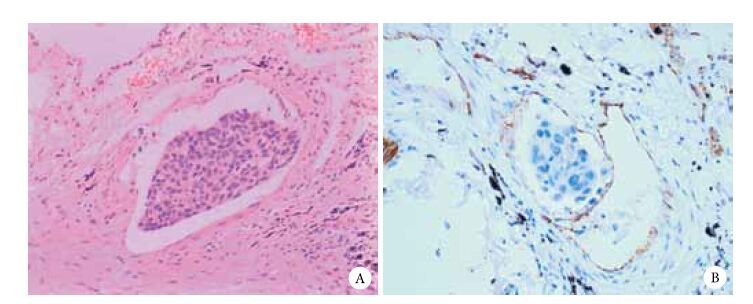

經多因素分析發現只有脈管浸潤(P=0.011)和腫瘤的直徑≥2 cm(P=0.026)是ⅠA期NSCLC患者預后不良的獨立危險因素(表 2)。脈管浸潤HE染色及免疫組化病理學結果見圖 1。生存曲線見圖 2和圖 3。

注:A:HE染色 ×20;B:免疫組化染色CD31陽性 ×200